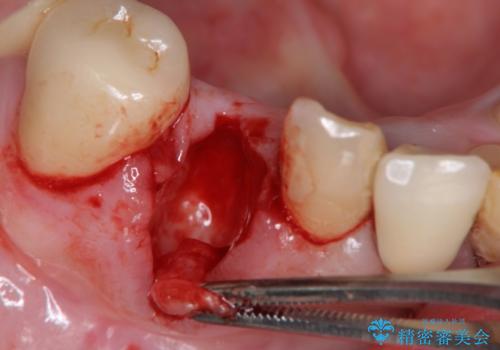

X線写真および歯周組織検査より、歯の破折 周囲骨の高度な吸収が認められました。

抜歯後、インプラントによる審美・機能改善を希望されたのでインプラント埋入に先立ち吸収した骨の再生を計画します。